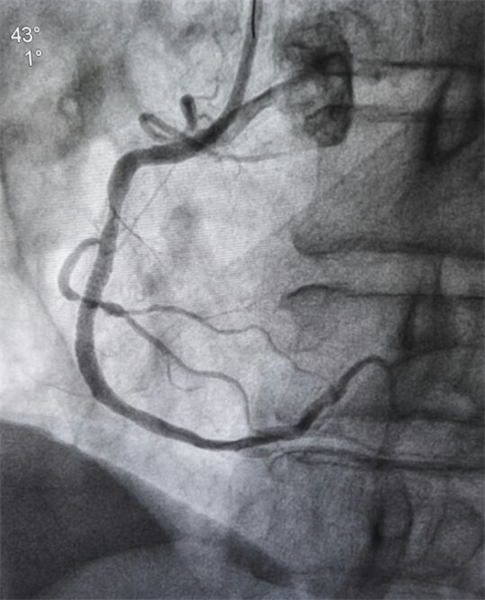

治疗后

近日我院刷新开展冠心病介入手术以来抢救急性心肌梗死最快纪录,从病人进入导管室到手术结束只用20分钟。患者余某某,男,59岁,因“胸痛不适半月加重五小时”于2017-04-18 10:08分入院,入院诊断:急性心肌梗死。2017-04-18 11:50分,患者开始进行冠状动脉造影术,10分钟造影结束,20分钟支架释放,开通闭塞血管,手术成功,患者恢复良好。这例成功的案例为我院胸痛中心起了一个良好的开头。